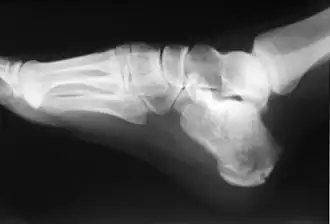

Le calcanéus peut subir des fractures.

Radio d'une fracture du calcanéus.